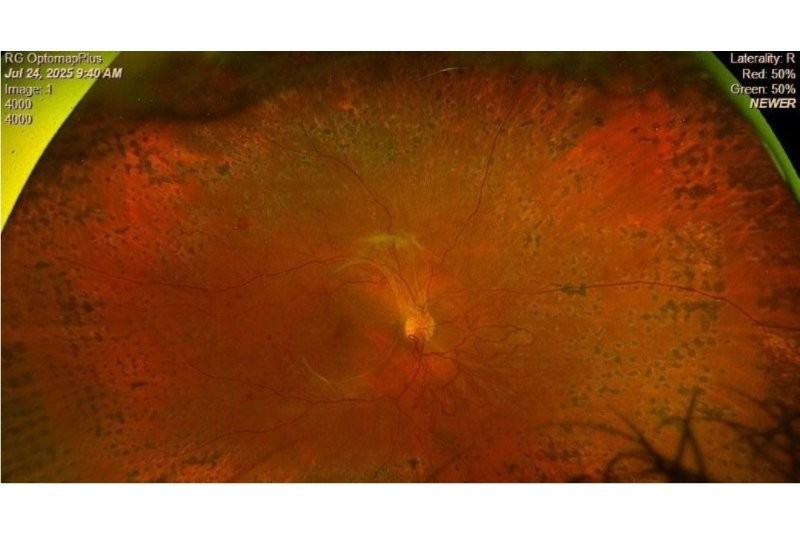

A peripheral exudative haemorrhagic chorioretinopathy lesion in an 80-year-old. Optos Silverstone’s image “helps confirm the lesion is not a choroidal mass but instead a subretinal/subRPE haemorrhage,” says Dr Stephen Guest

The Optos captures the horizontal meridian better than any other widely available technologies. The ability to perform widefield (and particularly temporal) fluorescein/ICG angiography is very useful for characterising some of the more unusual conditions, such as retinal vasculitis, FEVR (familial exudative vitreoretinopathy), PEHCR (peripheral exudative haemorrhagic chorioretinopathy) and Coats disease, where you need to know what's happening in that far periphery.

With choroidal naevi, the Optos peripheral OCT capability gives information on the height of the lesion and whether the naevus has subretinal fluid or not, which can be a sign of potential malignant transformation. Differentiating a retinoschisis from a chronic atrophic peripheral retinal detachment is another useful OCT application, guiding your decision as to whether observation or active management is required.